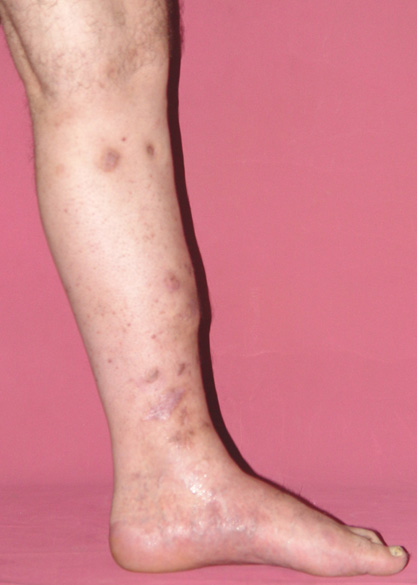

Kas ve iskelet sistemi enfeksiyonları, sık karşılaşılan bir sorundur. Yeni evreleme sistemleri, gelişmiş cerrahi teknikler, ve hiperbarik oksijen tedavisi gibi destek tedavileri sayesinde kronik osteomiyelit tedavisi son 20 yıl içinde büyük ölçüde değişmiştir.

Kronik osteomiyelit, kemik ve yumuşak dokularda nekroza yol açar. Ölü kemik, patojen mikroorganizmalara ev sahipliği yapan bir nidus oluşturur. Konağın savunma sistemleri, mikroorganizmalarla baş etmek için sıklıkla optimal koşullarda değildir. Dolaşım bozukluğu yüzünden enfeksiyon bölgesine antibiyotikler yeterince ulaşamaz. Bu nedenle ölü dokuların ortamdan tamamen uzaklaştırılması gerekir (radikal debridman).